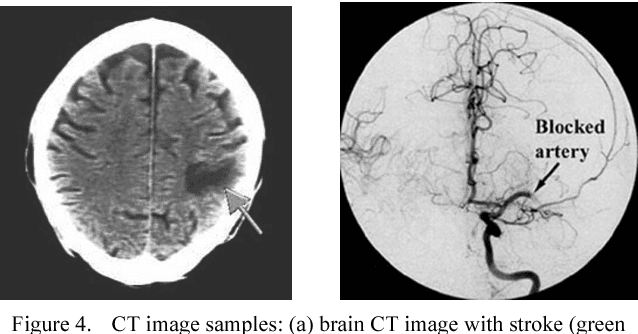

Abstract:We present a new system based on tracking the temporal evolution of stroke lesions using an image registration technique on CT exams of the patient's brain. The system is able to compare past CT exams with the most recent one related to stroke event in order to evaluate past lesions which are not related to stroke. Then, it can compare recent CT exams related to the current stroke for assessing the evolution of the lesion over time. A new similarity measure is also introduced for the comparison of the source and target images during image registration. It will result in a cheaper, faster and more accessible evaluation of the acute phase of the stroke overcoming the current limitations of the proposed systems in the state-of-the-art.